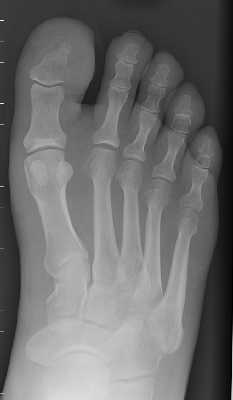

The above images show both the pre-operative and post-operative left foot of the same

patient. The pre-op film demonstrate osteomyelitis of the distal first phalanx that

was treated with a great toe amputation.